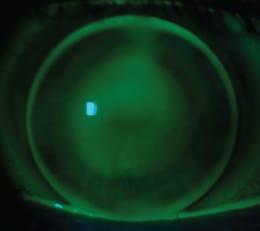

This 23-year-old woman with bilateral keratoconus had intracorneal ring implants in both eyes. She complained of poor vision, contact lens intolerance and many prior GP lens fittings with different specialists. Her best-corrected visual acuity with spectacles was 20/40. She was disappointed that she did not have better quality vision. Figure 4 shows the anterior segment upon evaluation.

Figure 4. Intracorneal ring segments very close to each other at 8 o'clock.